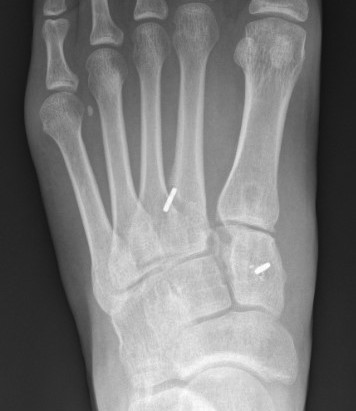

Fleck sign

Fleck sign with inter-cuneiform widening